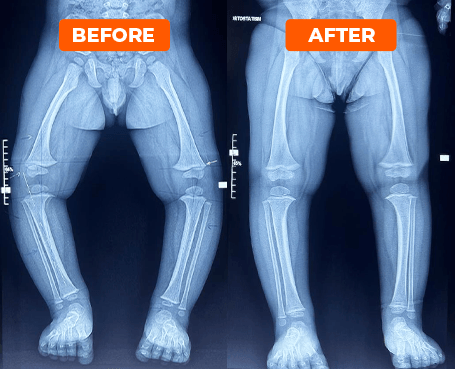

Rezultate care vorbesc de la sine